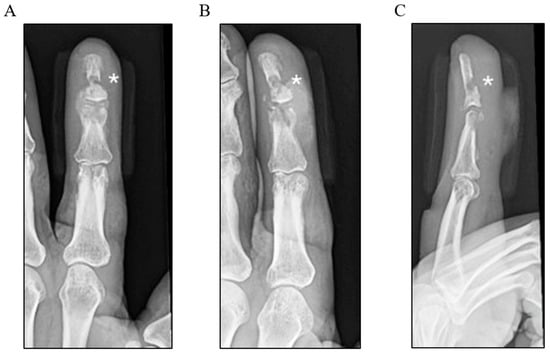

Intravenous antibiotics were recommended at this stage due to the failure of repeated oral treatments. However, the patient declined hospital admission because of personal and logistical challenges. Despite counselling on the risks of an untreated infection, including progression and the possible loss of the affected digit, efforts to persuade him were unsuccessful. The patient did, however, agree to outpatient imaging to assess the extent of the infection. A plain radiograph performed approximately 1 month post-injury demonstrated soft tissue swelling and clear bony erosions involving both the distal and middle phalanges, raising a high suspicion for osteomyelitis (Figure 1). An urgent referral was made to the plastic and reconstructive surgery unit; however, due to ongoing personal circumstances, the patient further delayed his presentation.

Figure 1. Three-view plain X-ray radiographs of the left index finger: (A) posteroanterior, (B) oblique, and (C) lateral views, labelled with * highlighting the bony erosions of the distal and middle phalanges.